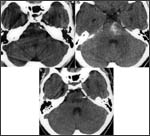

La internarea initiala computer tomograful indica rezultate normale, fara modificari cerebrale. Cu toate acestea, statusul neurologic al pacientului se degradeaza, acesta are o sincopa si este transferat de urgenta la un nou spital. La sosirea in noua unitate pacientul se afla in coma.

Un nou CT realizat indica o mica zona hipodensa, localizata pontin, fara hemoragie. La o reanalizare a CT-ului precedent se poate distinge o artera bazilara hiperdensa .

La putin timp dupa tromboliza pacientul a prezentat din nou pupile simetric reactive. Un nou CT indica o zona hiperdensa in regiunea centrala si laterala stanga a puntii. Aceasta corespunde unei mici hemoragii asimptomatice posttromboliza.